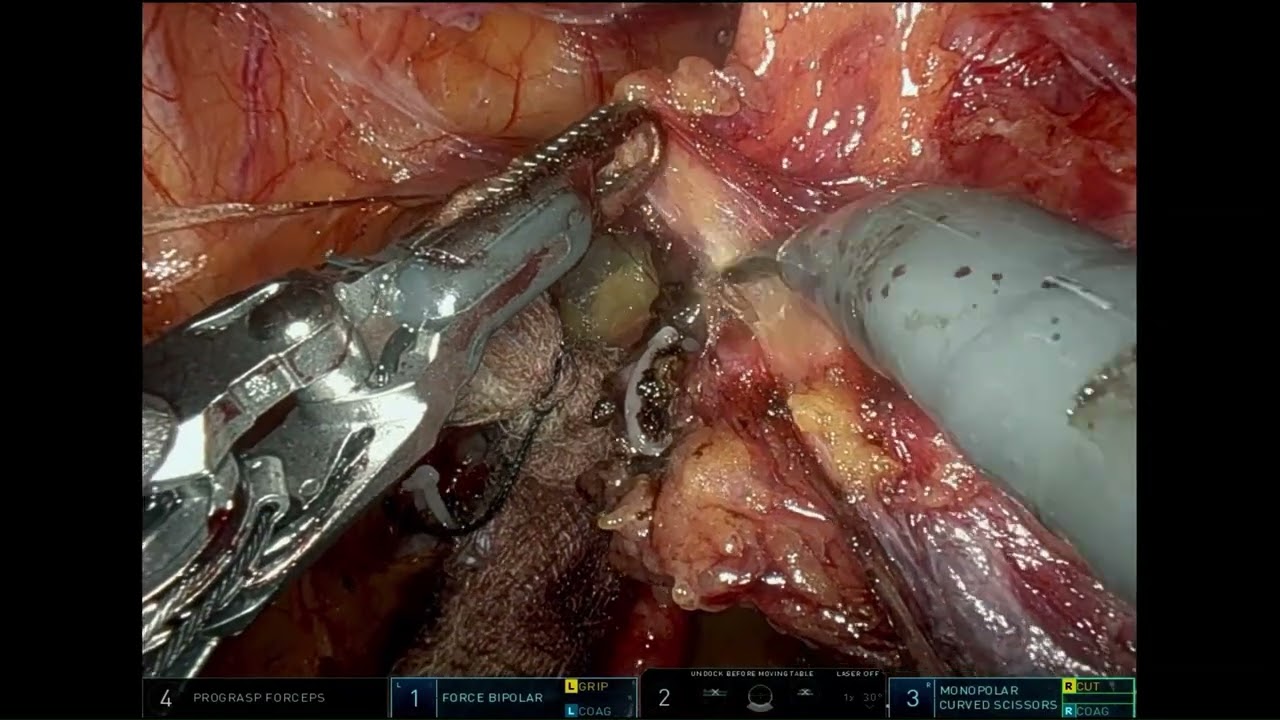

#219 Robot-assisted minimal invasive CABG using bilateral thoracic arteries- Dr. Michiel Algoet

KS Awards, Robotics, Surgeon ';